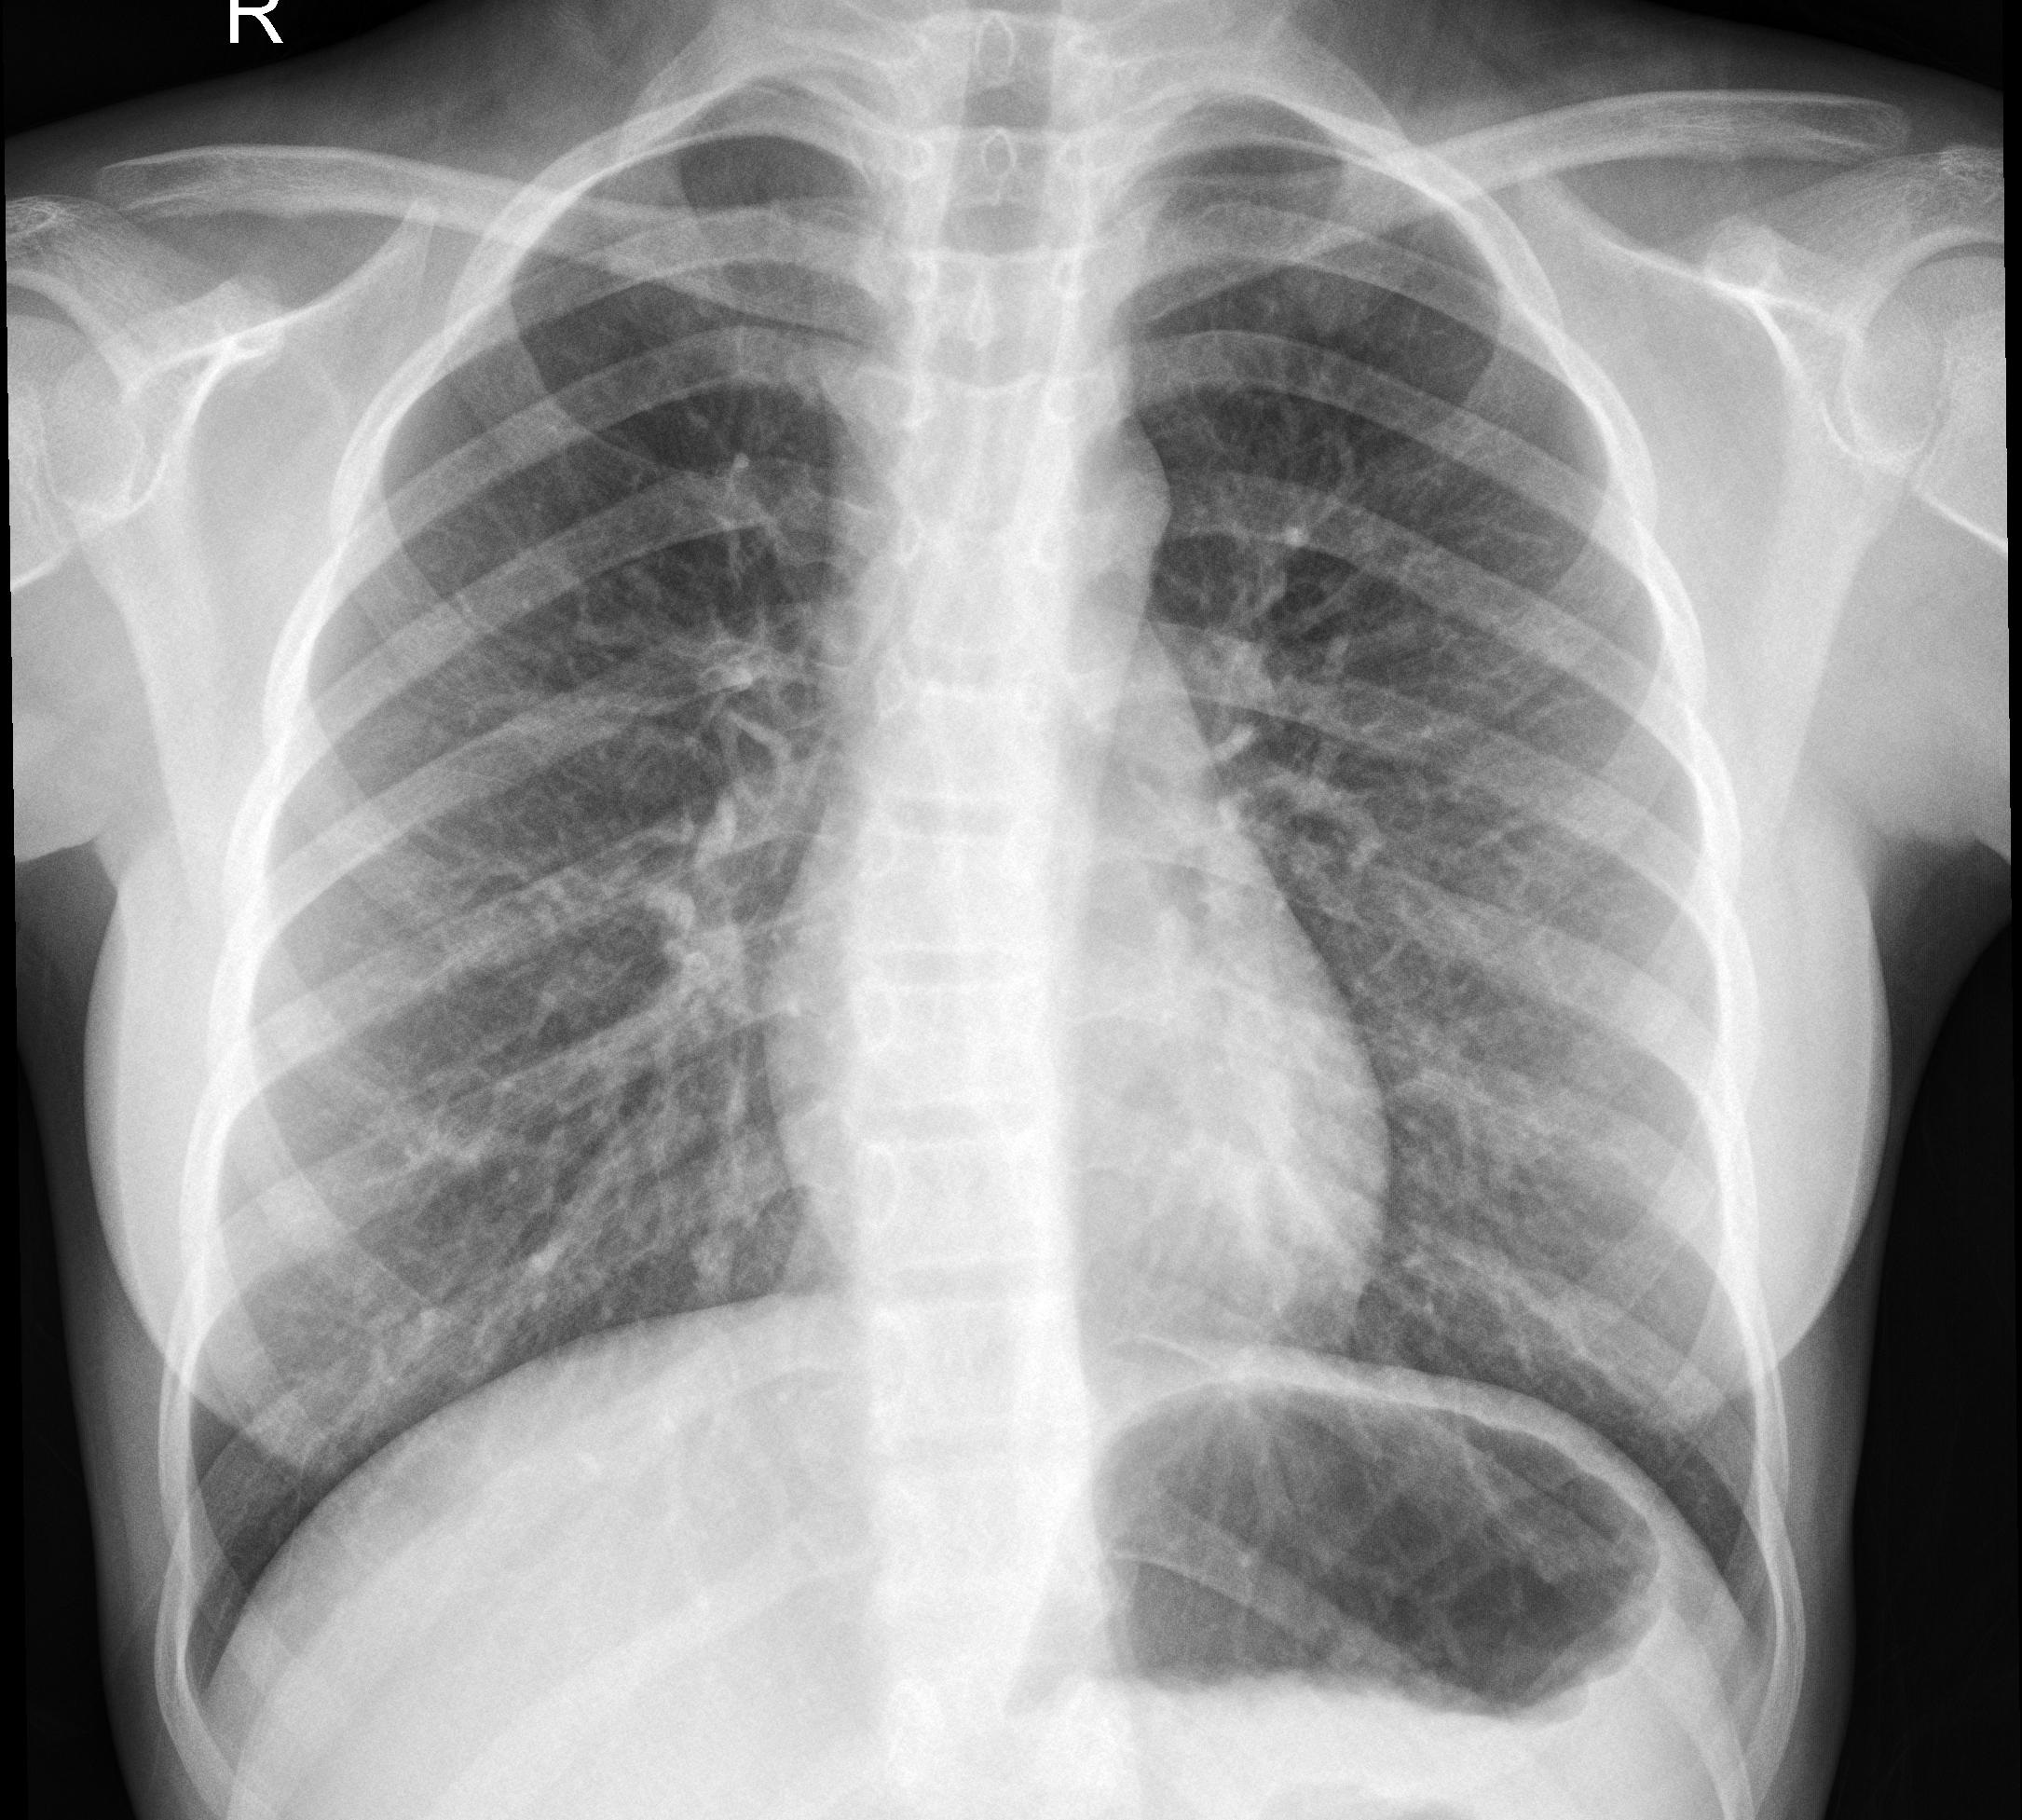

شیوع بیماری کرونا به قدری سریع بوده است که باعث کاهش سرعت عمل سیستم تشخیصی بیمارستان‌ها برای ارزیابی بیماران شده است. لذا تولید سریع کیت های تشخیص RT-PCR مهم تلقی میشد. به همین جهت تولید کیت ها با سرعت بیشتری ادامه یافت، ولی اینکار همراه با کاهش دقت و بی‌استفاده بودن آنها بود. مطالعه بیشتر علائم ویروس منجر به سطح بندی بیماران با فاکتور های تب و تنفسی گردید. بدین صورت که تب بالا و اختلال در سیستم تنفسی از نشانه های وخامت اوضاع بیمار بودند. با آزمایش های صورت گرفته، در مراحل اولیه بیماری، تصاویر اشعه X از قفسه سینه دارای دقت تشخیص بیشتری نسبت به روش سنتی می‌باشد. به همین جهت اپلیکیشن شناسایی خودکار سطح بیماری از طریق تجزیه و تحلیل فاکتور های تصاویر X-ray معرفي شده است.

نمونه تصاویر افراد مبتلا به کرونا

بازه زماني بين عكسبرداري تا تشخيص در حدود پنج تا ده روز به طول مي‌انجامد. خطاهاي تصويربرداري، تشخيص راديولوژيست و خطاي پزشك از جمله موانع موجود در تشخيص صحيح مي‌باشند. با وجود سيستم تشخيص‌گر مبتني بر هوش مصنوعي، ميتوان اين بازه زماني را كاهش داده و خطاي تشخيصي را كمتر كرد.